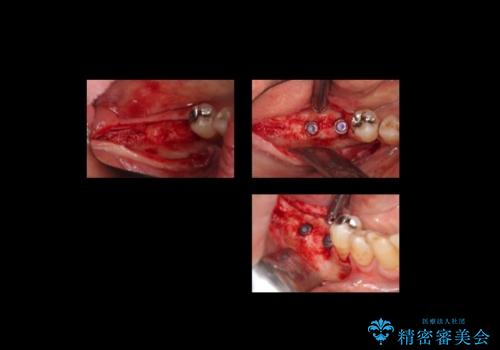

- 右下の奥歯が割れてしまい、抜歯を行いました。

ブリッジにできない位置であったため、インプラントでかめるようにしました。

- 約250万円 右下67 インプラント2本(ストローマンインプラント20万円、カスタムアバットメント10万円、シリンダーTeC 2万円 以上2本、マイナーGBR5万円) 再根管治療 (前歯 9万円x1、小臼歯11万円x1 大臼歯:専門医による再治療 15万円x3本) ジルコニアクラウン(右上2367、右下I6I7、左上56 10万円x8 )仮歯 1万円x8本 ファイバーコア 2万円x5 セラミックインレー(左上5) 7万円x1 フラットタイプナイトガード 3万円費用は治療当時の料金となります